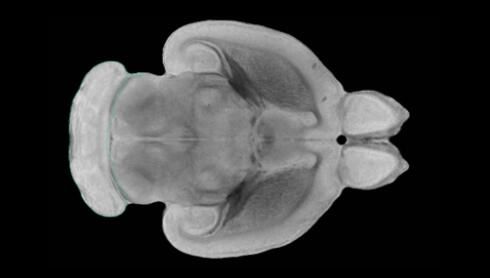

近日,一項(xiàng)刊登在國(guó)際雜志Nature上的研究報(bào)告中,來自劍橋大學(xué)的科學(xué)家們通過研究揭示了隨著年齡增長(zhǎng)大腦僵硬程度的增加導(dǎo)致大腦干細(xì)胞功能異常的分子機(jī)制,同時(shí)研究者還開發(fā)出了一種新方法能將老化的干細(xì)胞逆轉(zhuǎn)回年齡健康狀態(tài);相關(guān)研究結(jié)果有望幫助研究人員理解機(jī)體大腦的老化過程以及如何開發(fā)治療年齡相關(guān)大腦疾病的新型療法。

隨著機(jī)體年齡增加,肌肉和關(guān)節(jié)都會(huì)變得僵硬,這就會(huì)使得日?;顒?dòng)變得更加困難,本文研究表明,我們的大腦也是如此,與年齡相關(guān)的大腦僵硬對(duì)大腦干細(xì)胞的功能或許有著重要影響。文章中,研究人員對(duì)年輕和老化大鼠的大腦進(jìn)行研究闡明了年齡相關(guān)大腦僵硬對(duì)少突膠質(zhì)前體細(xì)胞(OPCs,oligodendrocyte progenitor cells)功能的影響。OPCs是一類對(duì)維持正常大腦功能非常重要的大腦干細(xì)胞,其對(duì)于髓磷脂的再生也非常重要,髓磷脂是神經(jīng)組織周圍的脂肪鞘,在多發(fā)性硬化癥中髓磷脂的再生常常會(huì)被損傷,機(jī)體老化對(duì)這些細(xì)胞的影響常常會(huì)誘發(fā)多發(fā)性硬化癥的發(fā)生,這些細(xì)胞的功能在老化的健康人群中同樣會(huì)下降。

為了確定老化OPCs的功能缺失是否可以被逆轉(zhuǎn),研究人員將來自老化大鼠機(jī)體的老化OPCs轉(zhuǎn)移到了年輕大鼠柔軟的海綿狀大腦組織中去,值得注意的是,這些老化的大腦細(xì)胞能夠重新恢復(fù)活力,其行為非常像年輕更加強(qiáng)壯的細(xì)胞。這項(xiàng)研究中,研究人員在實(shí)驗(yàn)室中開發(fā)出了具有可變僵硬程度的新型材料,并在受控環(huán)境下研究這些材料的生長(zhǎng)及其對(duì)大鼠大腦干細(xì)胞的影響,這些材料能被工程化改造具有和年齡或老化大腦相似的柔軟程度。